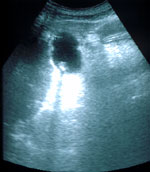

La utilidad de la ecografía es un hecho demostrado en los últimos años y prueba de ello es que se ha convertido en la técnica de elección ante cualquier sospecha de patología biliar (litiasis biliar, ictericia, colecistitis, tumores, etc.). La Ecografía puede informar con precisión del estado normal o patológico de la vesícula y de las vías biliares de forma rápida, cómoda, exenta de riesgos y con una alta sensibilidad y especificidad diagnósticas.